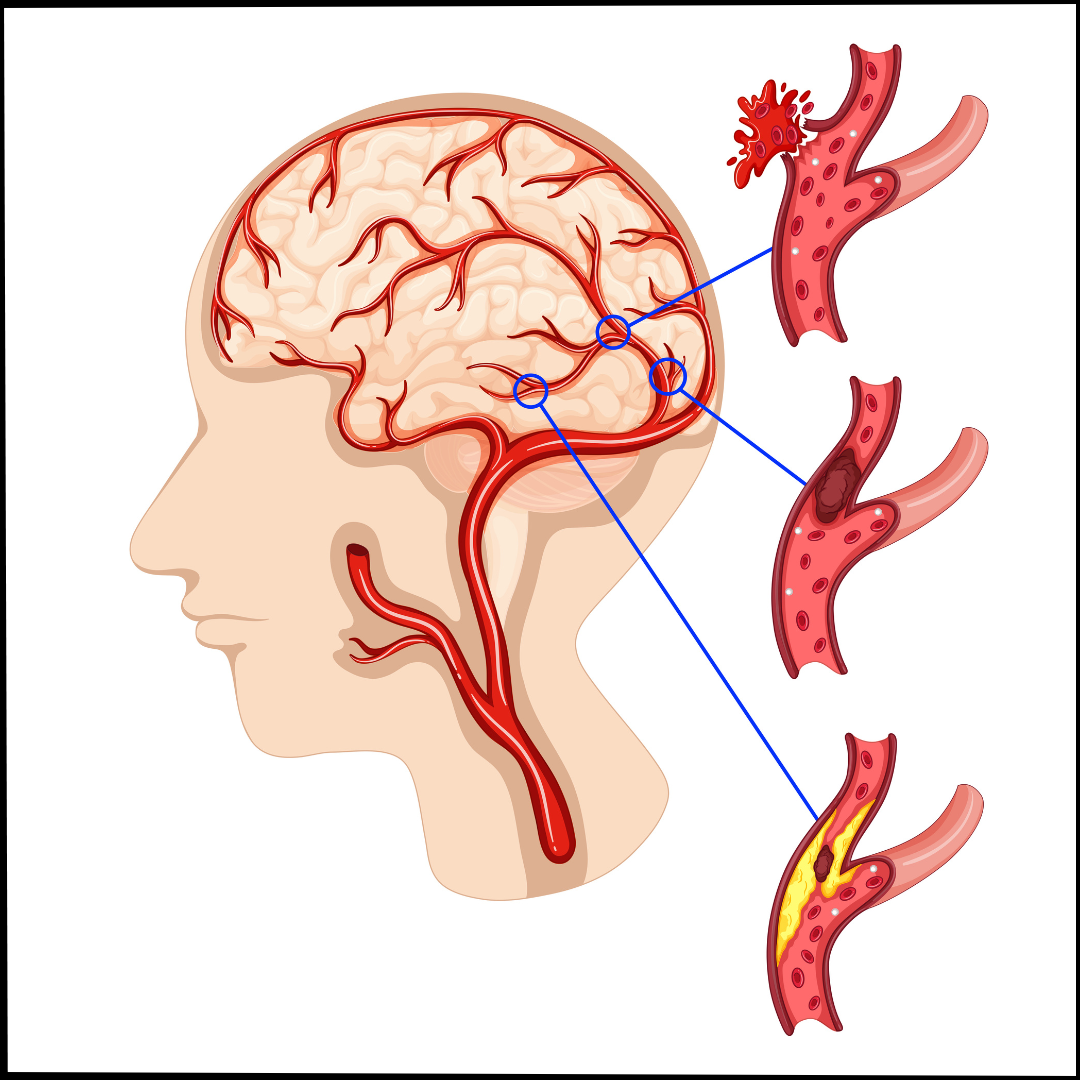

اختلالات عروقی مغز به مجموعه بیماریهایی گفته میشود که به دلیل مشکل در رگهای خونی مغز ایجاد میشوند و میتوانند جریان خون، اکسیژنرسانی و عملکرد طبیعی مغز را مختل کنند. این گروه از مهمترین علل سکته مغزی و آسیبهای عصبی پایدار هستند.

مغز برای عملکرد طبیعی به خونرسانی مداوم نیاز دارد. هر عاملی که باعث کاهش، قطع یا نشت غیرطبیعی خون در رگهای مغزی شود، میتواند به آسیب سلولهای مغزی منجر گردد.

1. سکته مغزی ایسکمیک (Ischemic Stroke) – شایعترین

به علت گرفتگی یا تنگی رگ مغزی ایجاد میشود.

2. سکته مغزی هموراژیک (Hemorrhagic Stroke)

به علت پارگی رگ مغزی و خونریزی ایجاد میشود.

4. ناهنجاریهای عروقی مغز

الف) آنوریسم مغزی (Aneurysm)

برآمدگی دیواره رگ که ممکن است پاره شود.

ب) ناهنجاری شریانی–وریدی (AVM)

اتصال غیرطبیعی بین شریان و ورید بدون مویرگ.

ج) کاورنوم (Cavernous Malformation)

تودهای از رگهای غیرطبیعی کوچک.